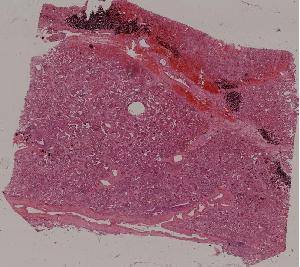

低倍视野

66. Active nodular cirrhosis of the liver

67. Inactive nodular cirrhosis of the liver